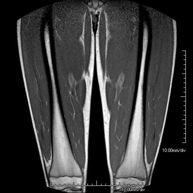

RM MuscularProva diagnòstica no invasiva que consisteix en l'obtenció d'imatges d'alta definició anatòmica de la musculatura que s'estudia mitjançant l'ús d'un camp electromagnètic i ones de ràdio (amb un emissor i un receptor). No utilitza radiació ionitzant. Poques vegades requereix l'ús de contrast paramagnètic (Gadolini) per a una millor definició de les lesions.